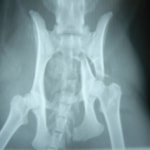

骨盤骨折 : 症例1 | 症例2 | 症例3 | 症例4

症例3:キルシュナーワイヤーのピンニングによる整復

ペルシャ猫 11ヶ月齢 雄

他院にて左大腿骨遠位の成長板骨折(salter-harrisⅠ型)が認められており、治療相談を目的として来院。当院にて、キルシュナーワイヤーを用いたピンニングにより骨折部位の整復を行いました。術後の経過は良好で、現在も経過観察中です。

術前レントゲン

術後レントゲン